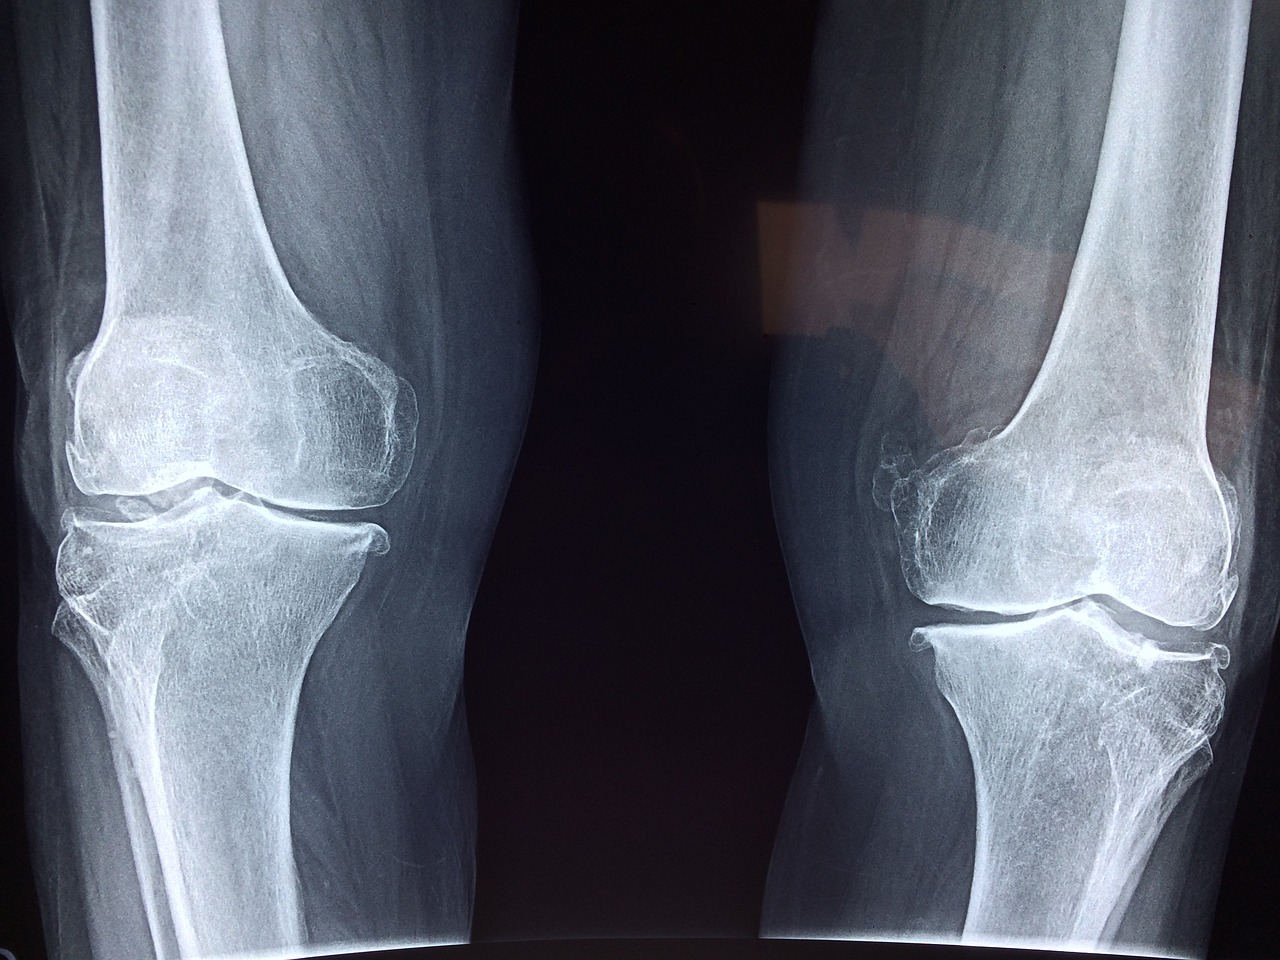

평생 써야 하는 관절! 💡

하지만 무리한 운동과 잘못된 습관이 오히려 관절을 손상시킬 수 있습니다.

한 번 손상된 관절은 회복이 어렵기 때문에 예방이 무엇보다 중요하죠.

✅ 달리기 시 무릎 관절은 체중의 7~9배 무게를 지탱해야 합니다.

✅ 과체중·비만이면 무릎에 가해지는 압력이 더욱 커져 관절 손상이 심해집니다.

✅ 비만한 사람은 정상 체중보다 ‘무릎 관절 수술’ 확률이 40% 더 높습니다.